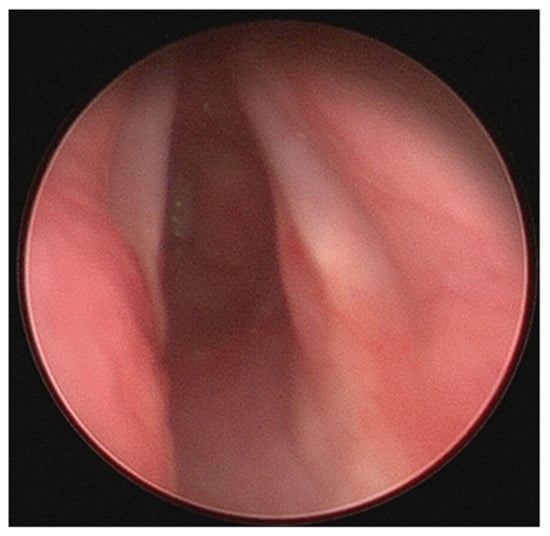

2.6. Tracheobronchomalacia